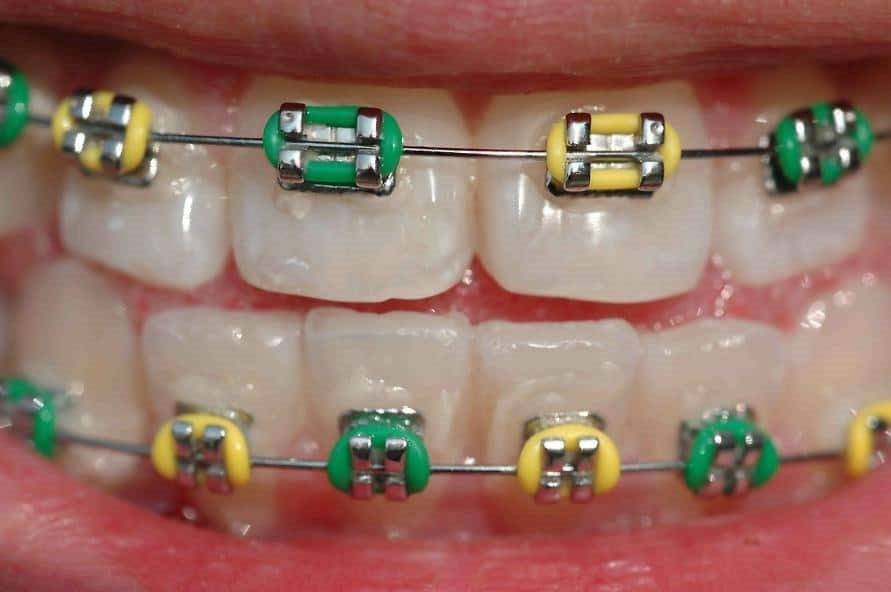

Лигатуры – это дополнительные элементы брекет-системы, которые удерживают дугу в пазу замочка. На начальном этапе лечения в качестве лигатур используются кусочки тонкой проволоки. Затем они заменяются на резинки. Основное назначение лигатур – обеспечение движения замочков вслед за изменяющейся формой дуги. Проволока фиксирует брекеты очень жестко, что часто приводит к неравномерной нагрузке на зубы. В связи с этим могут появиться ноющие боли, которые с трудом может переносить взрослый, не то, что ребенок. Резиночки прокрашиваются пишментами из пищевых продуктов и напитков, что требует их регулярной замены.

Нельзя сказать однозначно, какая из систем лучше. Каждая из них отлично справляется с задачей устранения дефектов зубных рядов. Сроки лечения не зависят от типа используемой конструкции. Пациенту придется посещать стоматолога для коррекции системы примерно с одинаковой частотой. Безлигатурные системы изготавливаются из самых разных материалов, что позволяет «поиграть» с формой и цветом. В лигатурных резиночки могут быть самых разных цветов, что при желании позволяет превратить ортодонтическую конструкцию в стильный аксессуар.